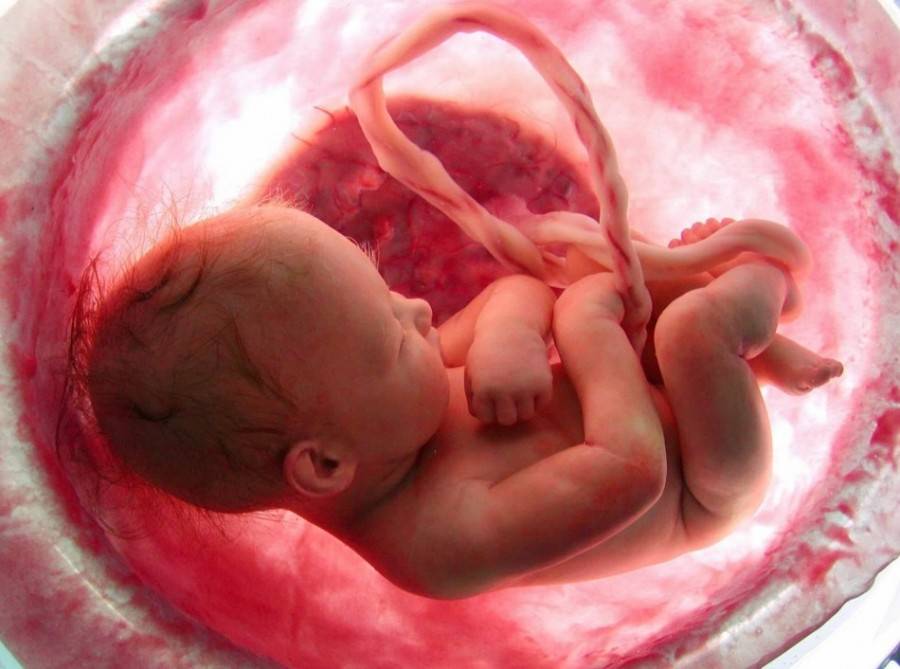

Развитие плода

Внутренние органы плода к 21 неделе заканчивают свое формирование, однако они еще не отлажены.

Почти все эндокринные железы уже выполняют свои функции: гипофиз, поджелудочная, щитовидная, надпочечники и половые железы.

На этой неделе у плода появляется вестибулярный аппарат. Его назначение — определять положение тела в пространстве.

Включается в работу селезенка.

Совершенствуется центральная нервная система (ЦНС) и ребенок бодрствует в период активности и отдыхает в период сна.

Пищеварительная система развита настолько, что малыш может заглатывать околоплодные воды, а желудок в свою очередь отделяет из них воду и сахар и пропускает вплоть до прямой кишки.

Развиваются вкусовые сосочки на языке ребёнка; очень скоро малыш сможет различать сладкое от соленого, горькое от кислого

(Внимание: вкус амниотической жидкости имеет прямую связь с питанием матери. Если мама увлекается сладеньким, то и жидкость будет сладкая, и малыш вырастет сластеной).

Образовываются лейкоциты, которые несут ответственность за защиту малыша от инфекций.

Почки в состоянии уже пропускать до 0,5 мл отфильтрованной жидкости, выводящейся в виде мочи.

Все «лишние» элементы начинают скапливаться в толстой кишке, превращаясь в меконий.

Продолжается рост лануго на головке малыша.